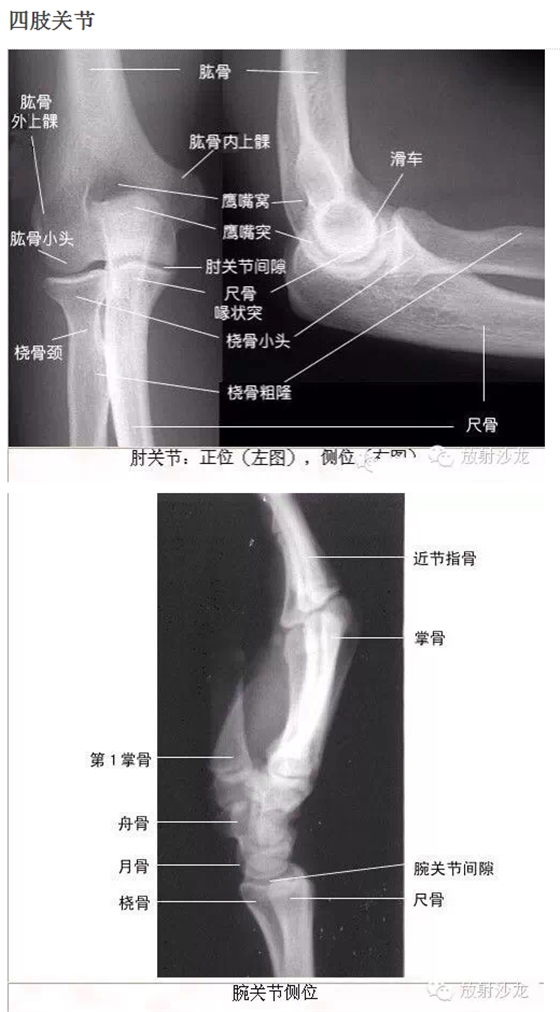

干貨!超級全的X線解剖圖